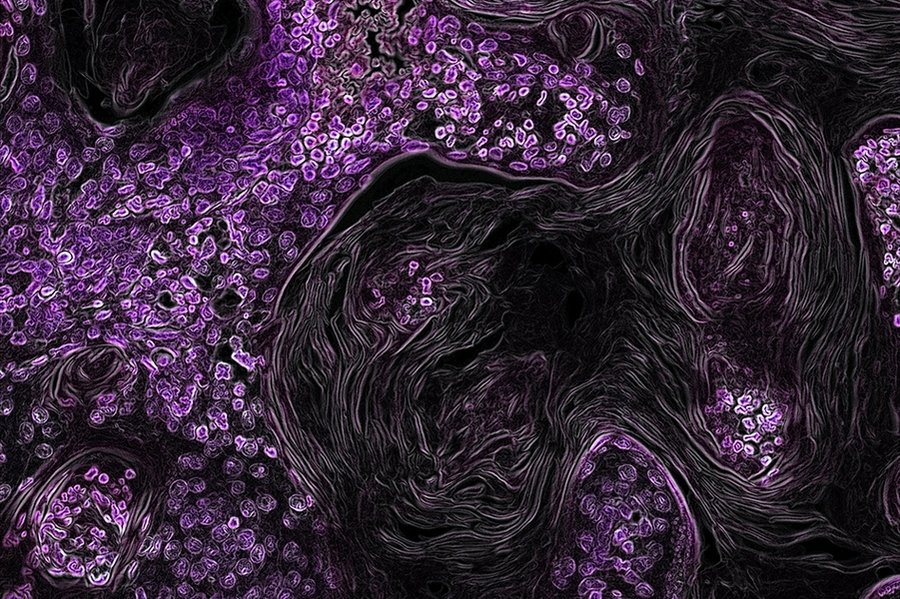

Caption: In this image, lung cancer driven by the KRAS oncogene shows up in purple. MIT biologists have found a potential new way to treat this type of lung tumor, long thought to be “undruggable."

In this image, lung cancer driven by the KRAS oncogene shows up in purple. MIT biologists have found a potential new way to treat this type of lung tumor, long thought to be “undruggable."